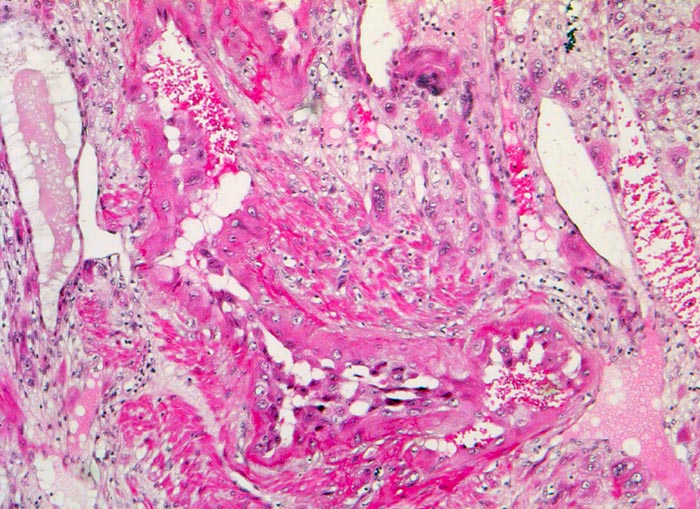

Gravidität

Plazenta

Zytotrophoblastzellen des extravillösen Zytotrophoblasten mit grossen hyperchromatischen Kernen invadieren nicht nur das

Myometrium, sondern auch die Spiralarterien der Dezidua.

Fetale Zellen sind im Lumen der mütterlichen Spiralarterie nachweisbar.

11. Schwangerschaftswoche. Normale Schwangerschaft